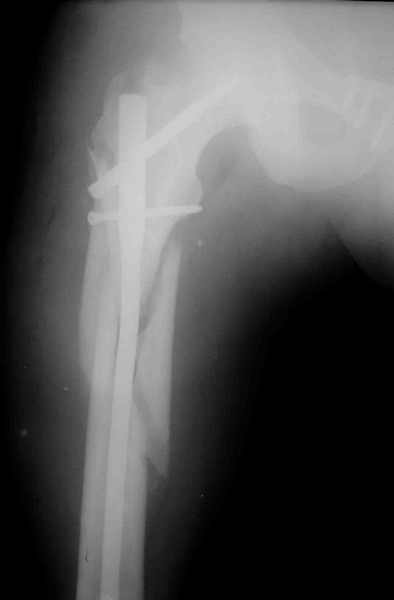

извините за опоздание , вот фотографии

Репозиция действительно очень неплохая, но чтобы уменьшить риск развития поздней нестабильности, в такой ситуации лучше выполнить синтез лонного сочленения пластиной и оставить аппарат месяца на 2.

В представленном случае повреждение несомненно ротационное и реальный диастаз как раз около пограничных 2,5 см, репозиция идеальная, достигнута в первые дни после травмы. Я бы ограничился 3 мес фиксации в аппарате с ограничением нагрузки первый месяц, и функциональными снимками в 6 -8 недель.